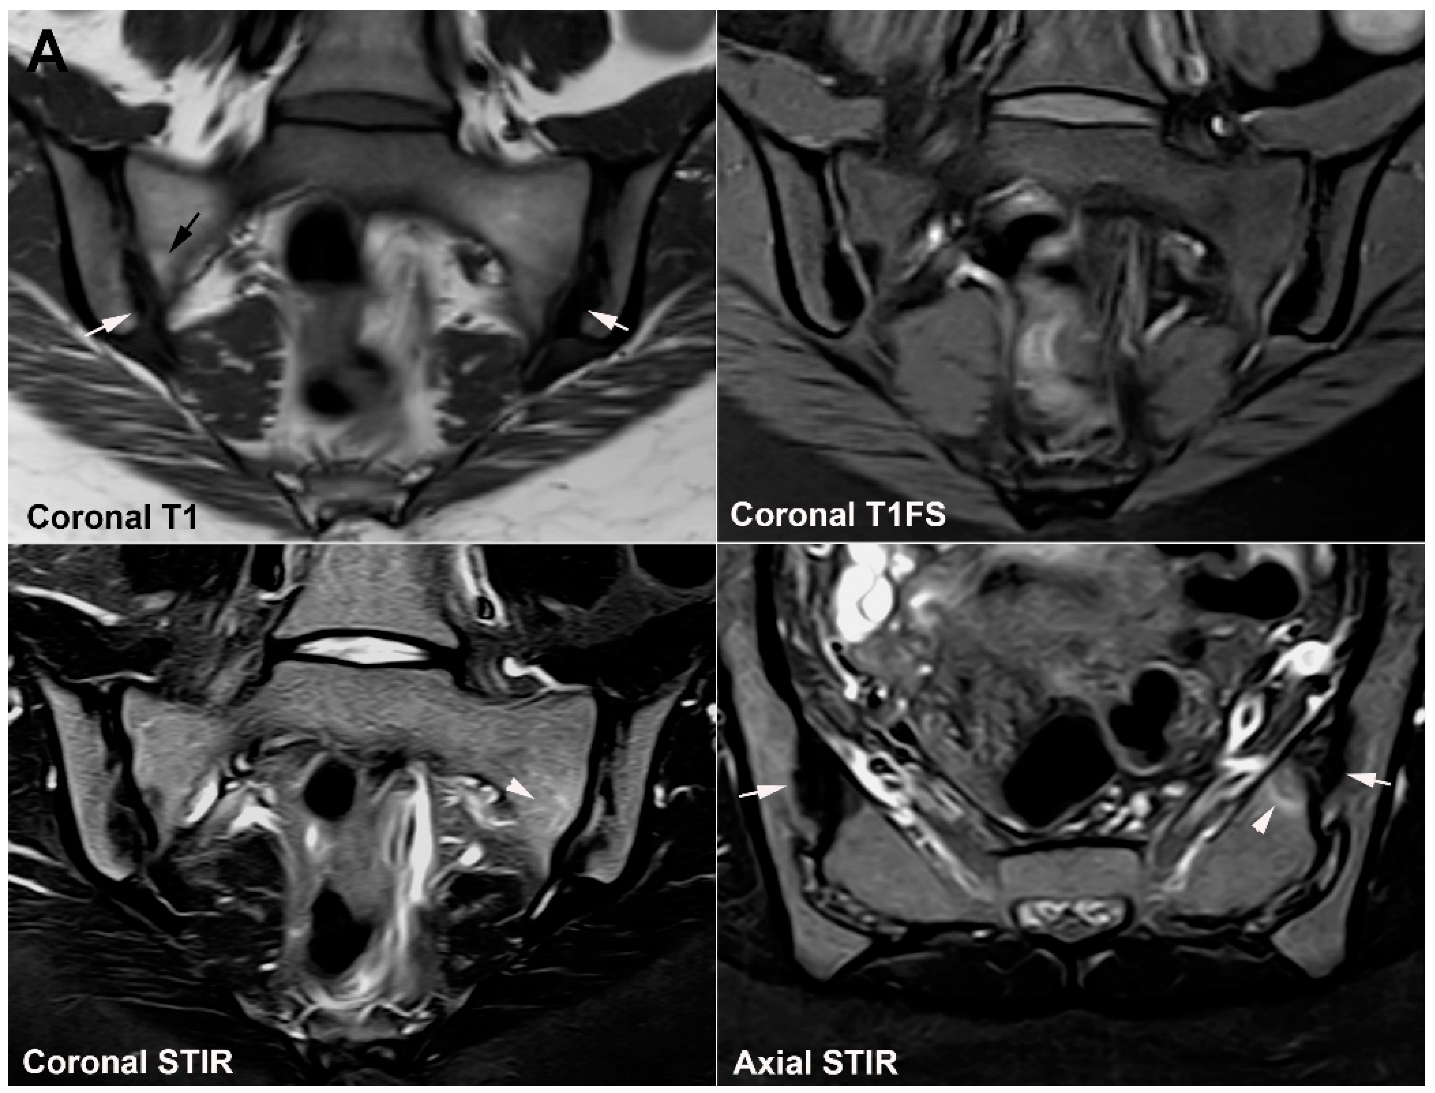

6. Other Strain-Related SIJ Changes

7. Degenerative SIJ Changes/Osteoarthritis